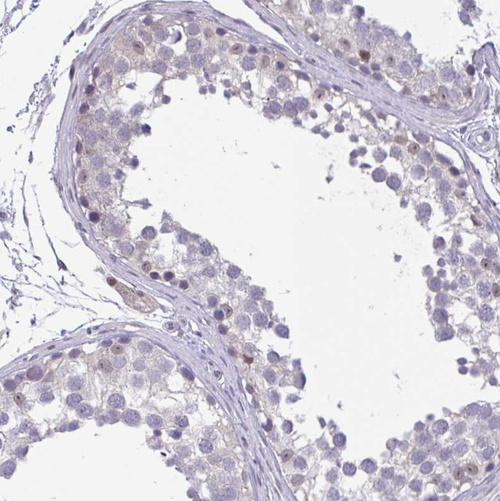

Immunohistochemical staining of human colon, kidney, liver and testis using Anti-RBL1 antibody HPA056525 (A) shows similar protein distribution across tissues to independent antibody HPA054962 (B).